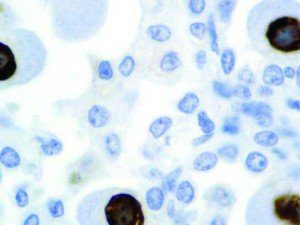

It is the ICU physician who is most likely to witness one of the deadliest manifestations of the abnormal immunological response, the cytokine storm syndrome (CSS). This response is also referred to by some as the cytokine release syndrome (CRS). CSS is characterized by continuous activation and expansion of macrophage and lymphocyte populations, which secrete large amounts of cytokines, causing the cytokine storm. This massive cytokine release is akin to hemophagocytic lymphohistiocytosis (HLH) disease, a syndrome characterized by initial unchecked and persistent activation of cytotoxic T lymphocytes and NK cells.

Clinical and laboratory manifestations of HLH include fever, enlarged liver and/or spleen, neurologic dysfunction, coagulopathy, liver dysfunction, cytopenias (i.e., low levels of erythrocytes, leukocytes, and/or platelets), hypertriglyceridemia, hyperferritinemia, hemophagocytosis, and eventually diminished NK cell activity as the immune system becomes progressively paralyzed. HLH can be familial (primary HLH) or secondary to another disease process (sHLH), such as rheumatic disease, in which it is referred to as macrophage activation syndrome (MAS, characterized by elevated ferritin).